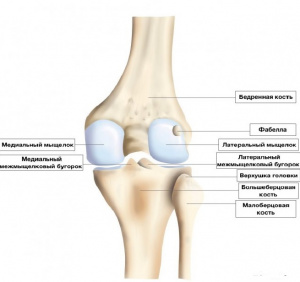

Анатомия: Блоки и сесамовидные кости в деталях